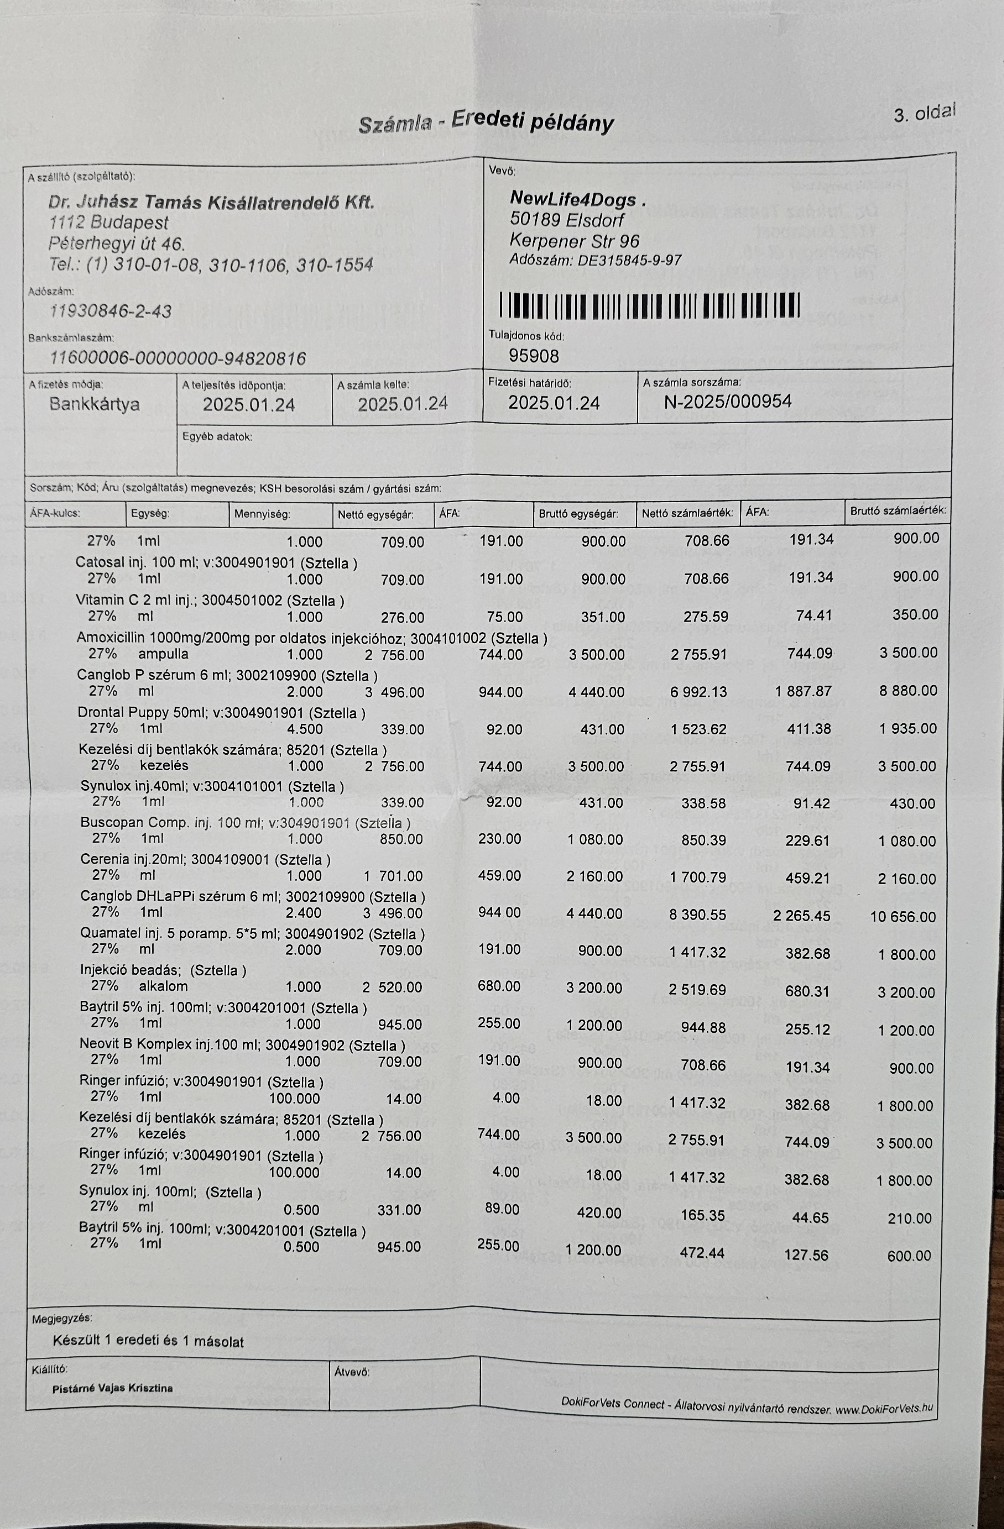

So zum Beispiel unsere kleine Stella, ein Welpen Mädchen das hier im Wald aufgefunden wurde. Nur 4 Tage nach Ankunft ging es Stella extrem schlecht und wir brachten sie in die Tierklinik zur stationären Aufnahme. Dort wurde sie intensivst medizinisch behandelt und musste 9 Tage in der Klinik verbleiben. Nur dieser eine Klinikaufenthalt verursachte Kosten in Höhe von 261.000,00 Forint ( ca. 640,00 Euro). Medikamente für die weitere Versorgung unserer Hunde musste bestellt werden. Ebenso Welpenfutter mussten wir nachkaufen. In den ersten Wochen wurden einige Hunde vergesellschaftet, damit die Quarantänestation wieder freie Zwinger hat. Denn in der Tötung warten Hunde darauf von uns abgeholt zu werden. Dies wird nun in den nächsten Tagen geschehen. Auch Klinikbesuche Kastrationen wurden wieder durchgeführt. Alleine hierfür betrug der finanzielle Aufwand ca. 750.000,00 (= ca. 1840,00 Euro) in der ersten Hälfte des Monats. Leider ist zur Zeit die Zeit extrem knapp, weswegen wir uns für die verspäteten Berichte entschuldigen. Doch die Rettungsaktionen und das Wohl unserer Schützlinge haben nun einmal Vorrang.

Nachdem die kleine Stella nach mehr als einer Woche die Klinik verlassen durfte, Mussten erneut einige unserer Neuzugänge dringende Not-OP´s und stationäre Aufnahme +ber sich ergehen lassen. So auch der kleine Sidney, den wir schwer verletzt mit gebrochenem Hinterbeinchen auf der Strasse in Nordungarn fanden. Sofortige Untersuchungen, Rüntgenaufnahmen und unverz+gliche Notoperation war erforderlich. Die Operation hat der kleine Mann gut überstanden. Nun benütigt er weitere Medikamente und Vitaminprodukte, damit er einen guten Heilungsprozess durchlaufen kann. Ebenso benütigt er 6 Wochen Zwingerruhe und Physiotherapie.

Auch unser lieber Oskar musste heute notfallmäßig in die Tierklinik. Aus derzeit noch unerklärlichen Gründen kann oskar sich nicht mehr auf seinen Hinterbeinen halten. Natürlich brachten wir ihn sofort in die Klinik. dort wurde er stationär aufgenommen. Nun ist eine MR untersuchung erforderlich, um die Ursache f+r die plützlichen Lähmungserscheinungen zu finden. Auch in der zweiten hälfte des Monats mussten wir wieder hohe Klinikkosten und Tierarztkosten bewältigen. Wir wären extrem erleichtert und dankbar wenn uns der ein oder andere hierbei unterst#tzen würde.